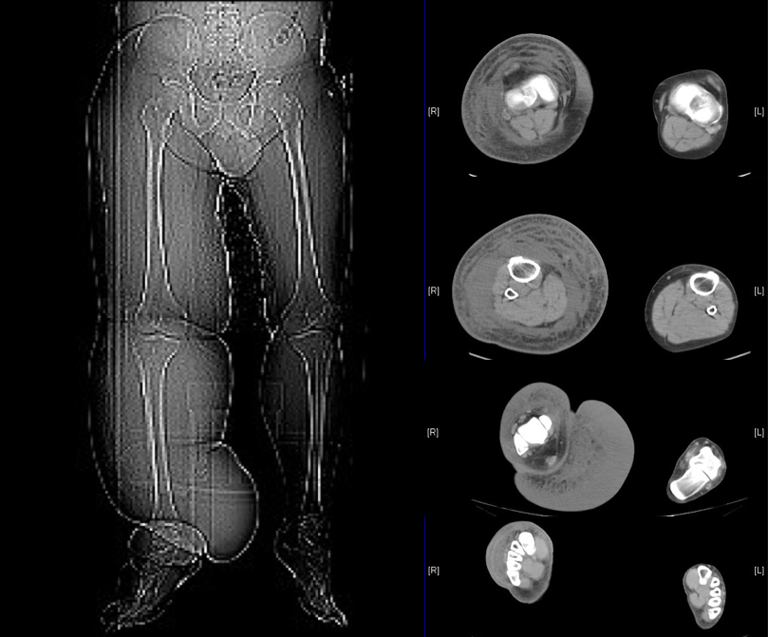

Diagnosis

If you're at risk of lymphedema, such as after cancer surgery involving your lymph nodes, your doctor might diagnose lymphedema based on your symptoms. If the cause is unclear, imaging tests may be ordered to examine your lymph system, including:

CT Scan